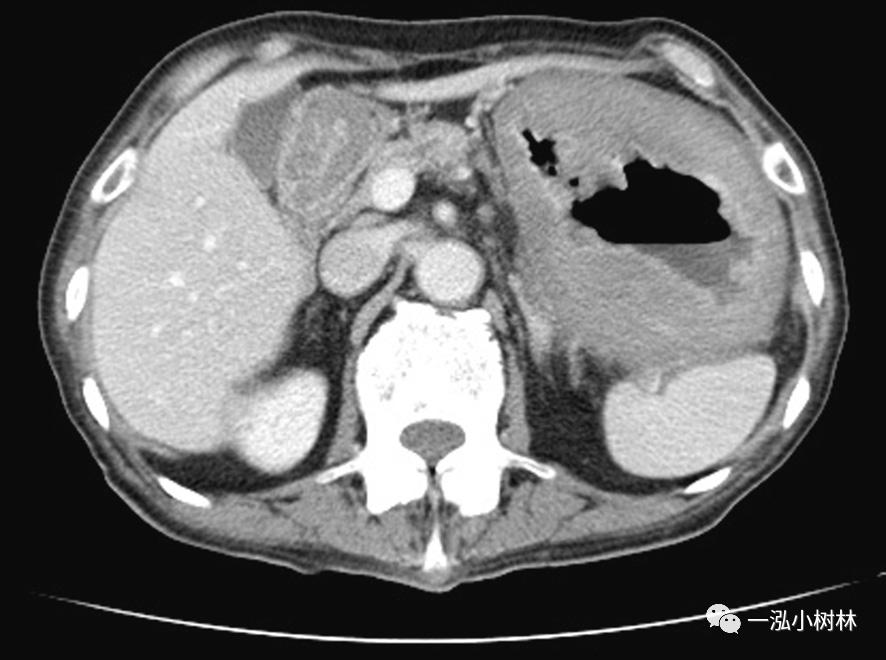

腹部CT检查(图3):胃壁弥漫性肥厚,整个胃呈肿块状。胃周围的淋巴结肿大和腹水不明显。

图3 腹部CT 胃壁弥漫性肥厚,胃周围淋巴结肿大和腹水不明显。